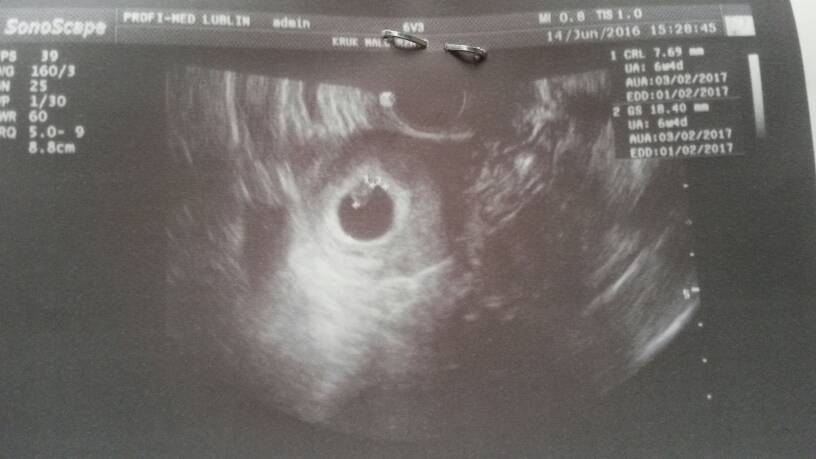

Gosiu super wieści ☺Jestem dziewczyny po wizyciewszystko dobrze. Ciąża niezagrozona, maleństwo ma 7,7mm serduszko ładnie bije. Wychodzi mi 6t4d i termin na 3 luty

Gratulacje kochana sliczne malenstwoJestem dziewczyny po wizyciewszystko dobrze. Ciąża niezagrozona, maleństwo ma 7,7mm serduszko ładnie bije. Wychodzi mi 6t4d i termin na 3 luty